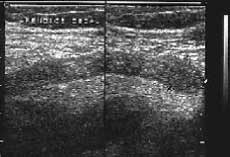

Рис. 6 и 7. (Слева) Воспаленный аппендикс в продольном сечении. Положение датчика косое. (Справа) Поперечное сканирование воспаленного изогнутого (на снимке дважды видно поперечное сечение) аппендикса.